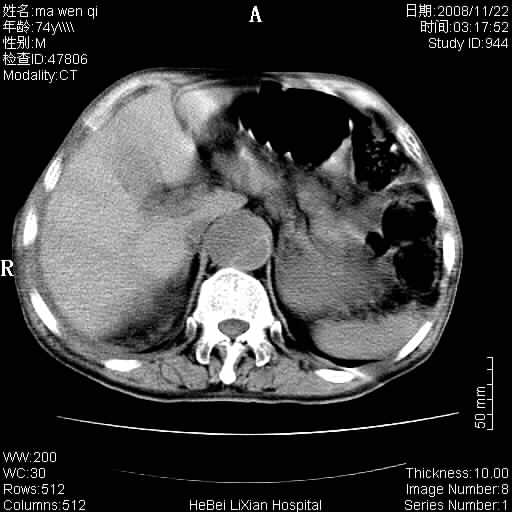

患者男 74岁.突然昏迷,休克6小时.血压70/30,头颅ct未见异常,既往体健.

补充病史,保留导尿10小时,尿袋内只有少许尿液,患者于住院后15小时后去世.

腹主动脉、双侧髂动脉夹层动脉瘤破裂出血进入腹腔。

1)考虑双侧髂动脉瘤并右侧动脉瘤破裂出血,右侧腹膜后及腹腔积血。2)双侧腹股沟疝。

1)考虑,腹主动脉、双侧髂动脉夹层动脉瘤破裂伴右侧腹膜后及腹腔积血。2)双侧腹股沟疝。

1)考虑胸、腹主动脉、双侧髂动脉瘤并右侧动脉瘤破裂出血,右侧腹膜后及腹腔积血。2)双侧腹股沟疝。